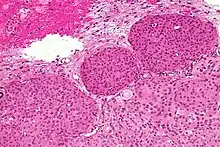

- Psammoma bodies (spheroid calcifications)

Histologically, meningioma cells are relatively uniform, with a tendency to encircle one another, forming whorls and psammoma bodies (laminated calcific concretions).[18] As such, they also have a tendency to calcify and are highly vascularized.